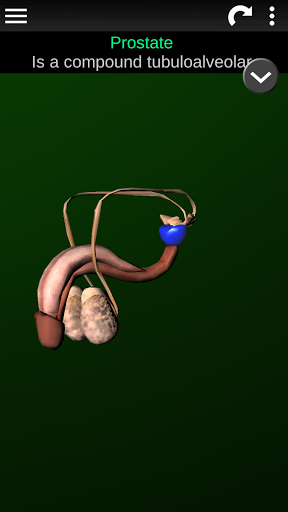

* Voortplantingssysteem, dat de mannelijke en vrouwelijke voortplantingsorganen omvat.

* Beschrijvingen van elk orgel.